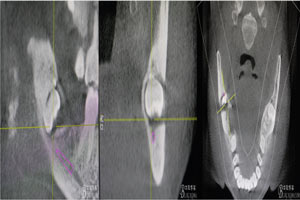

圖3.其他方向的影像檢查:48近中牙冠與下頜管之間無(wú)骨壁相隔。